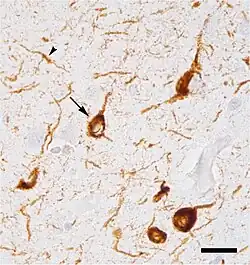

Micrograph of tauopathy (brown) in a neuronal cell body (arrow) and process (arrowhead) in the cerebral cortex of a patient with Alzheimer's disease. Bar = 25 microns (0.025mm).

Micrograph of tauopathy (brown) in a neuronal cell body (arrow) and process (arrowhead) in the cerebral cortex of a patient with Alzheimer's disease. Bar = 25 microns (0.025mm).